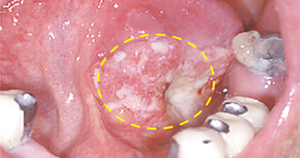

[혀의 아랫면에 발생한 편평상피세포암]

입천장에는 풍치와 증상이 비슷하게 잇몸이나 입천장이 부풀어 오르는 경우가 대부분으로 치주염에 의한 염증보다는 단단한 덩어리를 형성하게 됩니다. 틀니를 장착하신 분들은 이러한 혹 때문에 틀니가 잘 맞지 않게 됩니다.

[입천장에 발생한 침샘암]

[입천장에 발생한 편평상피세포암]

이 부위도 초기에는 잇몸에 발생한 염증이나 양성 종양과 유사하게 보일 수 있습니다. 진행되면 잇몸 주변의 치아를 둘러싸고 있는 치조골을 침범하기 때문에 치아가 흔들리게 됩니다. 더 진행하면 턱뼈를 침범하며 입술의 감각도 둔하게 됩니다. 간혹 치아를 뽑고 나서 상처가 아물지 않고 한 달 이상 지속적인 염증이 생기는 경우가 있습니다. 이러한 경우에는 잇몸에 발생한 구강암일 가능성도 있기 때문에 정밀한 검사를 받아보시는 것이 좋습니다.

[아래 잇몸에 발생한 구강암]